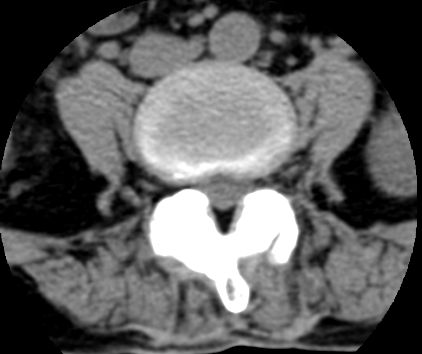

以下是引用余辉在2007-9-4 21:00:00的发言:[br]椎体棘突有点异常(像是被切割了),不知有否手术史,如椎体融合术等。单纯的退行性变可以出现椎间隙变窄,但同时一般会出现椎体上下缘的硬化增生,且椎体间完全融合的机率更小,本例椎体完全融合且椎体上下皮质缘破坏掉了,如果没有手术史,就应该考虑椎间盘炎性病变了,且椎体棘突及棘间韧带的变化也并不是不支持这个,多数小关节也融合了,且其形态也容易让人联想到如强脊炎及类风关等病变。[br][br][本贴已被 余辉 于 2007-9-4 21:03:55 修改过]

以下是引用chry3在2007-9-4 20:42:00的发言:[br]椎间盘病史?是什么样的病史,无双下肢放射痛,那就不是椎间盘突出了。是感染、什么性质的?[br]从图象看椎间隙消失,椎间盘组织未见,锥体滑脱是因为椎间盘溶解造成的[br]l4、5椎体骨质结构未见异常,l5上缘是l4的长期压迫所致[br]还是考虑椎间盘感染,结核。[br]